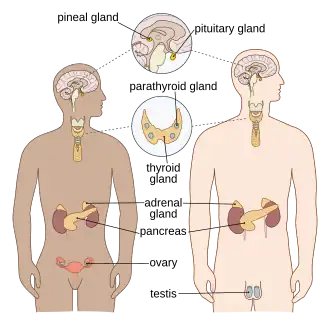

Endocrine system

The endocrine system consists of the principal endocrine glands: the pituitary, thyroid, adrenals, pancreas, parathyroids, and gonads, but nearly all organs and tissues produce specific endocrine hormones as well. The endocrine hormones serve as signals from one body system to another regarding an enormous array of conditions, resulting in variety of changes of function.[30]